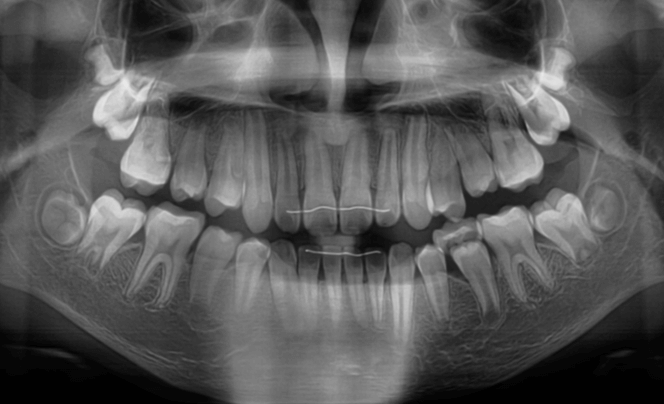

| 年齢・性別 | 8歳11ヶ月の男児 |

|---|---|

| 主訴 | 上顎の永久歯の位置がおかしいとのことで来院。萌出していない右上の前歯の状態に不安を抱えられていました。 |

| 治療期間・回数 | 約3年2ヶ月 |

| 費用 | 440,000円(税別) |